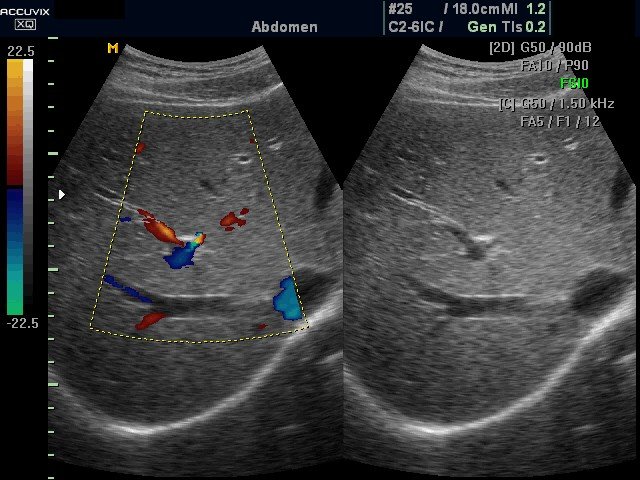

УЗИ сканер Accuvix-XQ (Medison, снят с производства)

Accuvix XQ - ультразвуковой сканер компании Medison экспертного класса (версия XQ) с цветным, двунаправленным энергетическим, тканевым, импульсным и непрерывноволновым допплером, трехмерное УЗИ в реальном времени (3D обычными и 4D объемными датчиками).

Области применения: акушерство и гинекология, абдоминальные исследования и маммология, урология и эхокардиография, поверхностно расположенные органы и исследования сосудов, мускуло-скелетные исследования, а также педиатрия, неонаталогия, транскраниальные исследования, интраоперационные исследования, исследования с применением контрастных веществ.

- CFM - цветное допплеровское картирование;

- PD - энергетический допплер (в т.ч. 3D);

- steering - возможность изменения допплеровского угла в режимах CFM и PD;

- дуплексный и триплексный режим;

- Dual Live Mode (двойной динамический дисплей) - одновременное отображение на мониторе двух изображений в режимах В и В-цвет, в реальном масштабе времени.

- в M-режиме вычисляются значения параметров для левого желудочка, аорты и левого предсердия, митрального клапана, а также частота сердечных сокращений. - Пакет расчетов параметров сосудов: вычисления объёмного кровотока, процента стеноза, индекса сопротивления (RI), пульсационного индекса (PI) и др.